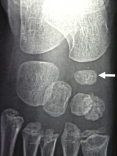

Exemple d'ostéochondrite de l'os scaphoïde (naviculaire) chez un garçon de 5 ans:

Les deux photos de gauche montrent un os densifié et aplati sur le pied gauche.

Les deux photos de droite montrent les mêmes radios sur le pied droit sain.